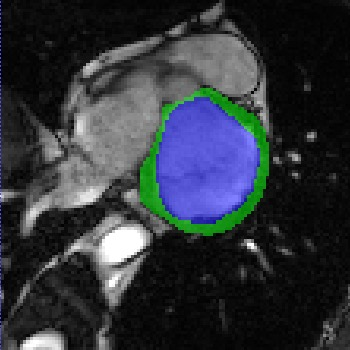

Transformers, the default model of choices in natural language processing, have drawn scant attention from the medical imaging community. Given the ability to exploit long-term dependencies, transformers are promising to help atypical convolutional neural networks (convnets) to overcome its inherent shortcomings of spatial inductive bias. However, most of recently proposed transformer-based segmentation approaches simply treated transformers as assisted modules to help encode global context into convolutional representations without investigating how to optimally combine self-attention (i.e., the core of transformers) with convolution. To address this issue, in this paper, we introduce nnFormer (i.e., Not-aNother transFormer), a powerful segmentation model with an interleaved architecture based on empirical combination of self-attention and convolution. In practice, nnFormer learns volumetric representations from 3D local volumes. Compared to the naive voxel-level self-attention implementation, such volume-based operations help to reduce the computational complexity by approximate 98% and 99.5% on Synapse and ACDC datasets, respectively. In comparison to prior-art network configurations, nnFormer achieves tremendous improvements over previous transformer-based methods on two commonly used datasets Synapse and ACDC. For instance, nnFormer outperforms Swin-UNet by over 7 percents on Synapse. Even when compared to nnUNet, currently the best performing fully-convolutional medical segmentation network, nnFormer still provides slightly better performance on Synapse and ACDC.